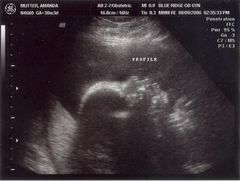

May 31, 2006: Diagnostic Ultrasound

OBs regularly do these to check if babies have all the right number of arms, brains, etc.

It's a girl! After getting this picture, my parents got to stop researching boys' names and circumcision.